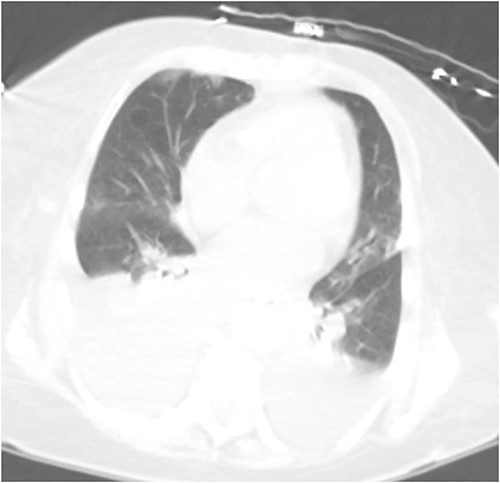

Computed tomography (CT) chest demonstrating bilateral pleural effusions.